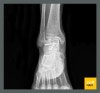

▥ 발목 골절 건설 현장에서 일용직 근무하시는 L 님은 작업 발판을 설치하시다가 추락하는 사고를 당하셨습니다. 검사 결과, 거골 개방성 골절 S9211 외 인대 파열, 탈구 등이 있었고, 안정적인 뼈의 유합을 위해서 정복술 및 고정물을 삽입하는 수술을 받으셨어요.

흔히 철심 박는다고 말하는, 이러한 수술 후에는 재활 역시 매우 중요합니다. 발목 관절 부위이다 보니 오랫동안 고정된 상태로 있게 되면 강직 현상으로 움직임에 제한이 생길 수 있기 때문이죠.